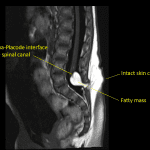

- Low-lying spinal cord terminating at the level of L5

- Associated T1/T2 hyperintense mass measuring 14 x 12 x 12 mm with signal suppression on STIR. This mass extends from the neural placode posteriorly through a spinal canal defect into the posterior paraspinal soft tissues

Low-lying spinal cord terminating at the level of L5. Associated T1/T2 hyperintense mass measuring 14 x 12 x 12 mm with signal suppression on STIR, suggesting fatty composition. This mass extends from the neural placode posteriorly through a spinal canal defect into the posterior paraspinal soft tissues. These findings are consistent with a lipomyelocele.

Sacral spinal dysraphism.

- Premature disjunction results in closed neural tube defects (i.e. defects with skin covering) where mesodermal elements are interposed within an incompletely closed neural tube that separates from the ectoderm, including:

- Lipomyelomeningocele – lipoma-placode interface located outside of the spinal canal

- Lipomyelocele – lipoma-placode interface located inside of the spinal canal

- This case is an example of a lipomyelocele because there is an intact skin covering, a fatty mass extending through a spinal canal defect, and the lipoma-placode interface is located within the spinal canal